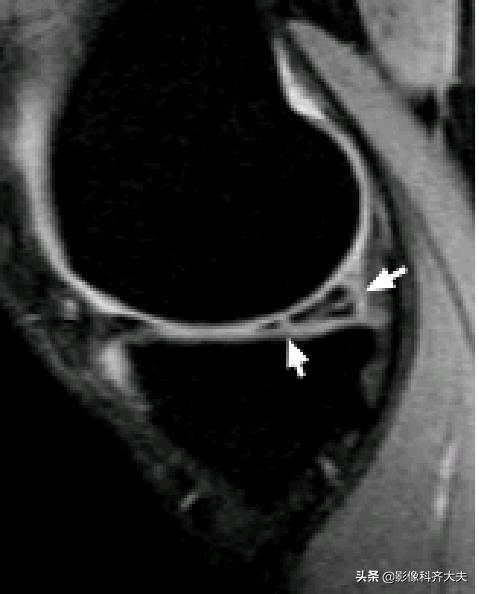

容易误诊为半月板损伤的正常解剖结构

膝横韧带:

腘肌腱腱鞘:

后股板韧带:

关节内气体伪影:

内侧半月板后角上隐窝: